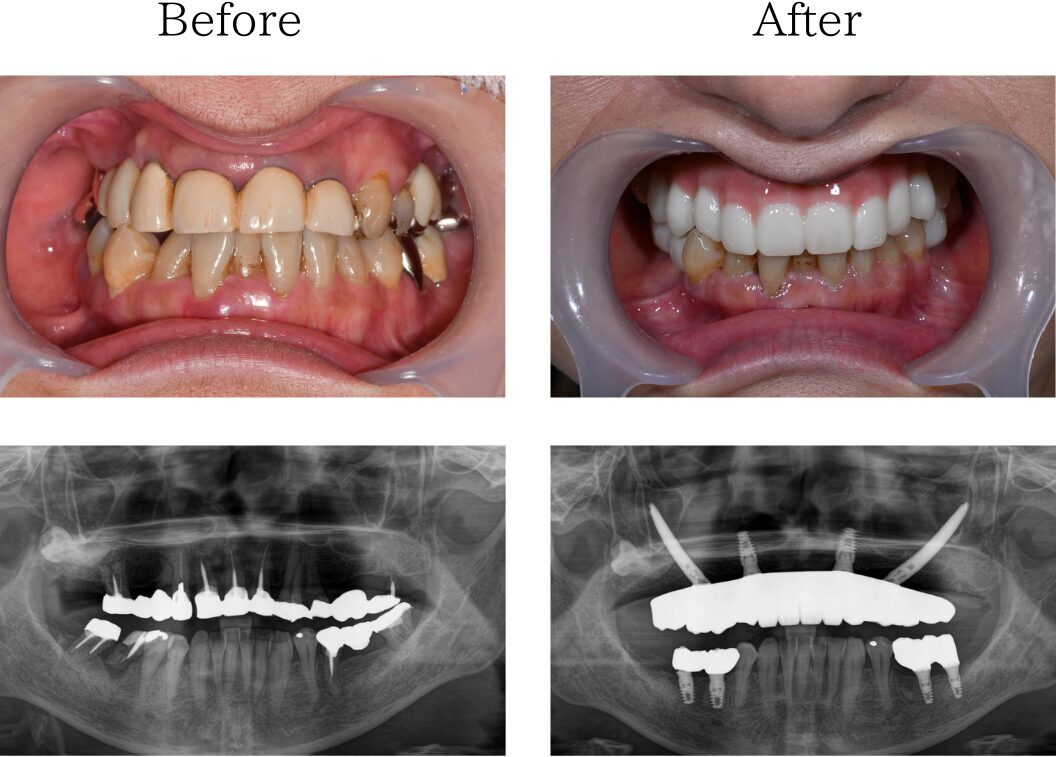

「入れ歯を卒業し、固定式の歯にしたい」

60代 男性(佐賀)の場合

上下入れ歯を使用していましたが取り外しが面倒なうえ、入れ歯自体も合わず痛みがあり満足に食事もできなかったです。何度通っても治らない治療にも嫌気がさし、全部一気にできる治療はないかと調べたところ、一日で固定式の歯が入るというおおたわ歯科医院のホームページを見て自分が理想としている治療だと思い、相談しました。

難症例 インプラント

※治療内容:上下顎オールオン4

※費用:3,760,000円*モニター価格

※期間:半年

※リスク:出血、痛み、腫れ、しびれ

「苦手な人付き合いを克服したい」

40代 女性 (大分) の場合

私は人付き合いが苦手で、歯医者に行くにしても何か思われたらどうしようと思い、治療に通えませんでした。そのせいで虫歯をそのままにして歯が溶けたり、歯が抜けてもそのままにしていたらボロボロになり、差し歯をしてもすぐ外れたりしてどの治療が合うのか分かりませんでした。ネットで調べていたところオールオン4という治療があることを知り、遠方ですがHPに記載されていた大多和先生の言葉を信じ福岡での治療を決めました。

「悩みを一緒に解決したい」

50代 女性 (福岡) の場合

上の歯のブリッジがかたつき始め、食べ物が噛めなくなってきました。見た目も長年気になっていて、コロナ禍のマスク生活で口元を見られることは少なくなりましたが、それと同時に人前で口元を見せることに抵抗が生まれました。ブリッジのかたつきやかみ合わせ、長年悩んできた見た目も一緒にできる治療が良いと思いオールオン4手術を決意しました。